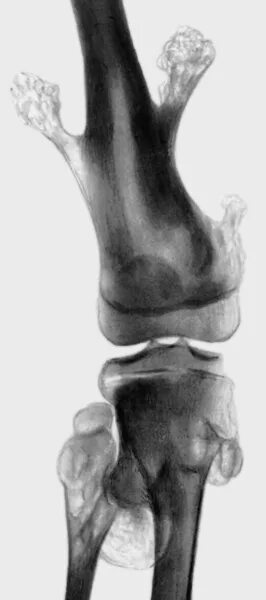

Экзостоз мкб 10